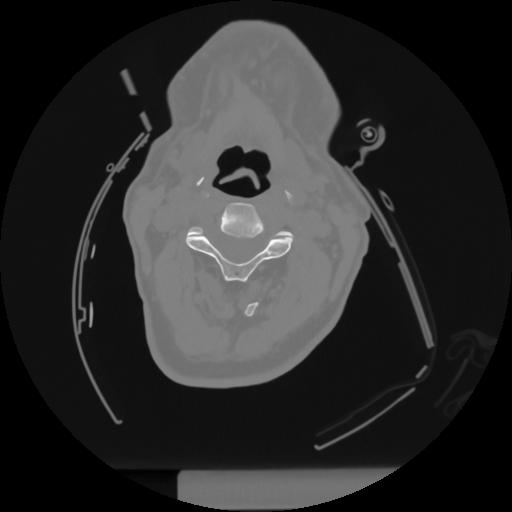

12 P.BLANDAS,,Vol,0.5,P.BLANDAS,,